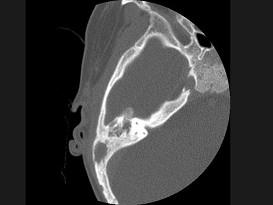

女性,17岁,右耳乳突区隐痛,右耳后乳突区出现包块,逐渐增大,CT检查如图所示,请选择最可能的 ( )